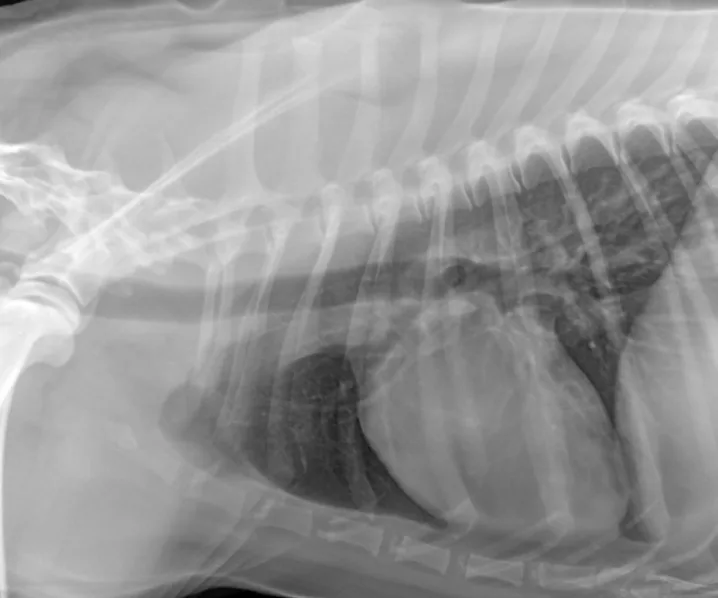

The patient recovered well and was discharged 7 days after admission. Outpatient therapy was continued with enrofloxacin at 10 mg/kg PO q24h, doxycycline at 5 mg/kg PO q12h, and amoxicillin trihydrate–clavulanate potassium (Clavamox, animalhealth.pfizer.com) at 13.75 mg/kg PO q12h 2 weeks after radiographic resolution of pneumonia (Figure 4) for a total of 7 weeks.

In follow-up films, alveolar infiltrates are completely resolved. There is a very slight increased nonstructured interstitial pattern within the left caudal lung lobe, which could be artifact as a result of mild to moderate leftward obliquity or possibly pulmonary fibrosis secondary to previous pneumonia. Courtesy Montrose Veterinary Clinic